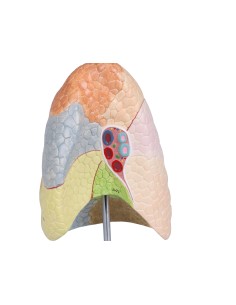

Dal cranio in 22 parti con incastri magnetici ai modelli di colonna vertebrale, da quelli di articolazioni a quelli di cuore, ogni pezzo della nostra collezione è progettato per un’immersione totale nello studio dell’anatomia umana. I nostri modelli, realizzati tramite scansioni di ossa vere, garantiscono un’esperienza tattile autentica e una fedeltà di peso quasi identica agli originali.

Essenziali per studenti e professionisti, i nostri modelli anatomici sono strumenti didattici che permettono di osservare le strutture anatomiche con precisione, eliminando la necessità di dissezioni o studi invasivi. Sono inoltre utili per spiegare ai pazienti le patologie, rendendo la comunicazione più efficace e risparmiando tempo prezioso.